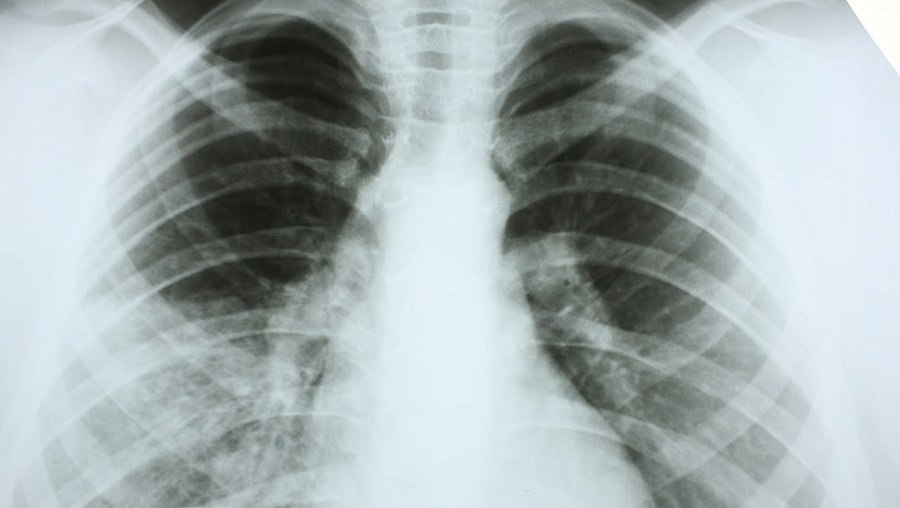

Растет заболеваемость пневмонией: как распознать опасность у себя и близких

Пневмония остается серьезным заболеванием, которое легко спутать с обычной простудой. Однако последствия промедления с лечением могут быть тяжелыми, о чем свидетельствует стопроцентная госпитализация всех выявленных на прошлой неделе случаев.